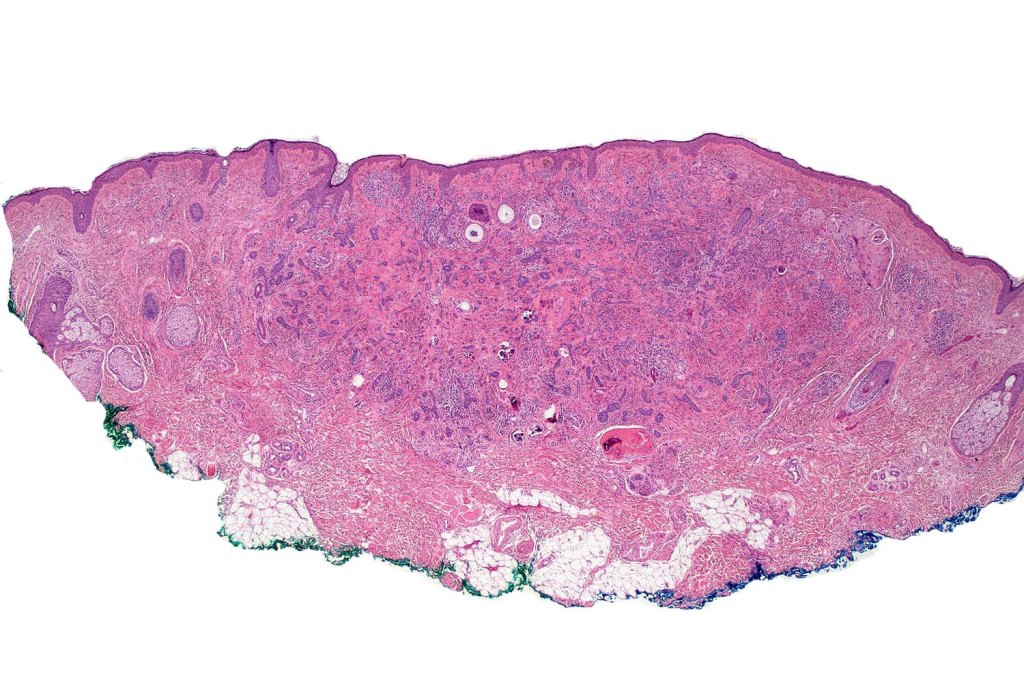

Histological features

•Consists of narrow epithelial strands & keratocysts embedded in a dense stroma

•Generally involves superficial & mid dermis but does not extend into the subcutaneous fat

•No evidence of glandular differentiation